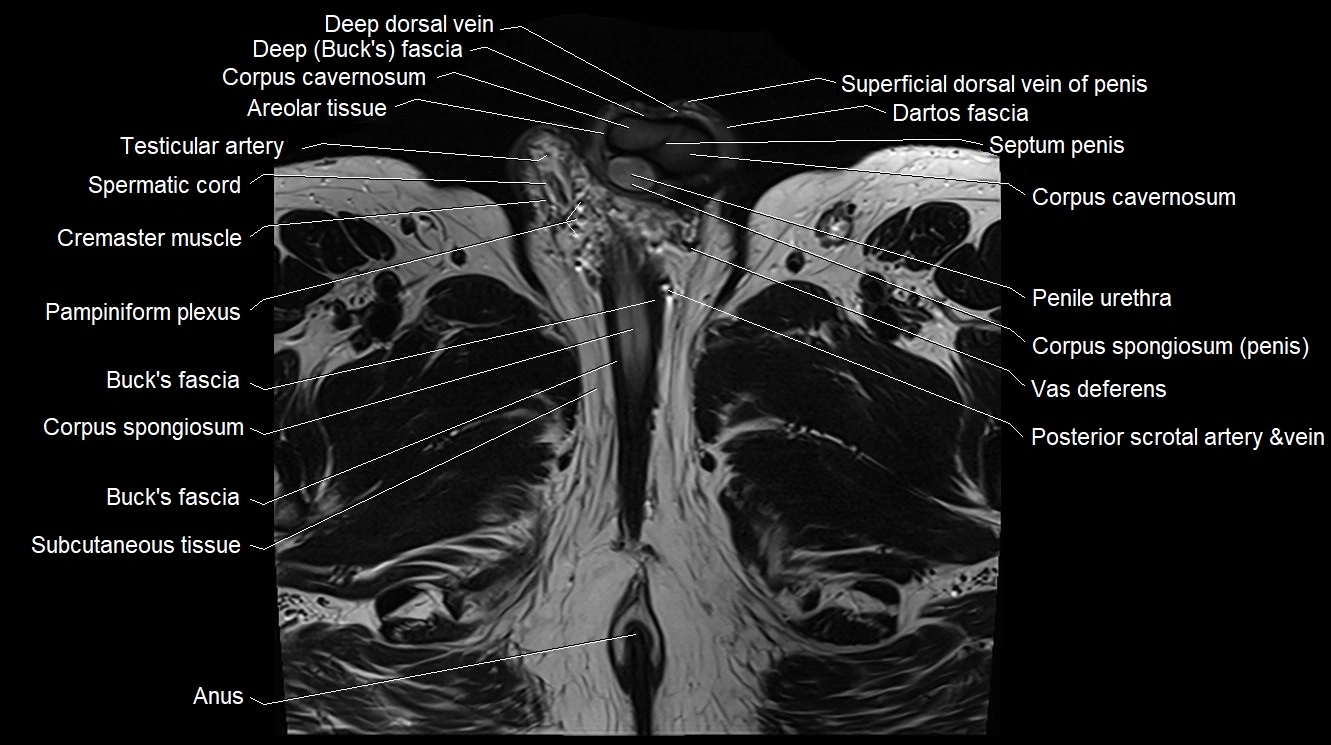

- Anal canal

- Areolar tissue of penis

- Buck's fascia (Deep fascia of penis)

- Corpus cavernosum

- Corpus spongiosum

- Cremaster muscle

- Dartos fascia

- Deep dorsal vein of the penis

- Pampiniform plexus

- Penile urethra

- Septum of the penis (Penile septum)

- Spermatic cord

- Subcutaneous tissue (scrotum)

- Superficial dorsal vein of penis

- Testicular artery

- Vas deferens